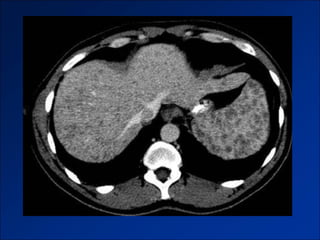

Hình ảnh trên CLVT

- Giai đoạn sớm:

+ Gan to.

+ Tăng tỷ trọng do xơ hóa.

- Giai đoạn muộn:

+ Gan biến đổi hình thái và đường bờ.

+ Dấu hiệu tăng ALTMC.

+ Dấu hiệu khác:

Dịch ascite – Lách to – Dày thành TM.

Nốt tân tạo.

Biến chứng (HCC).